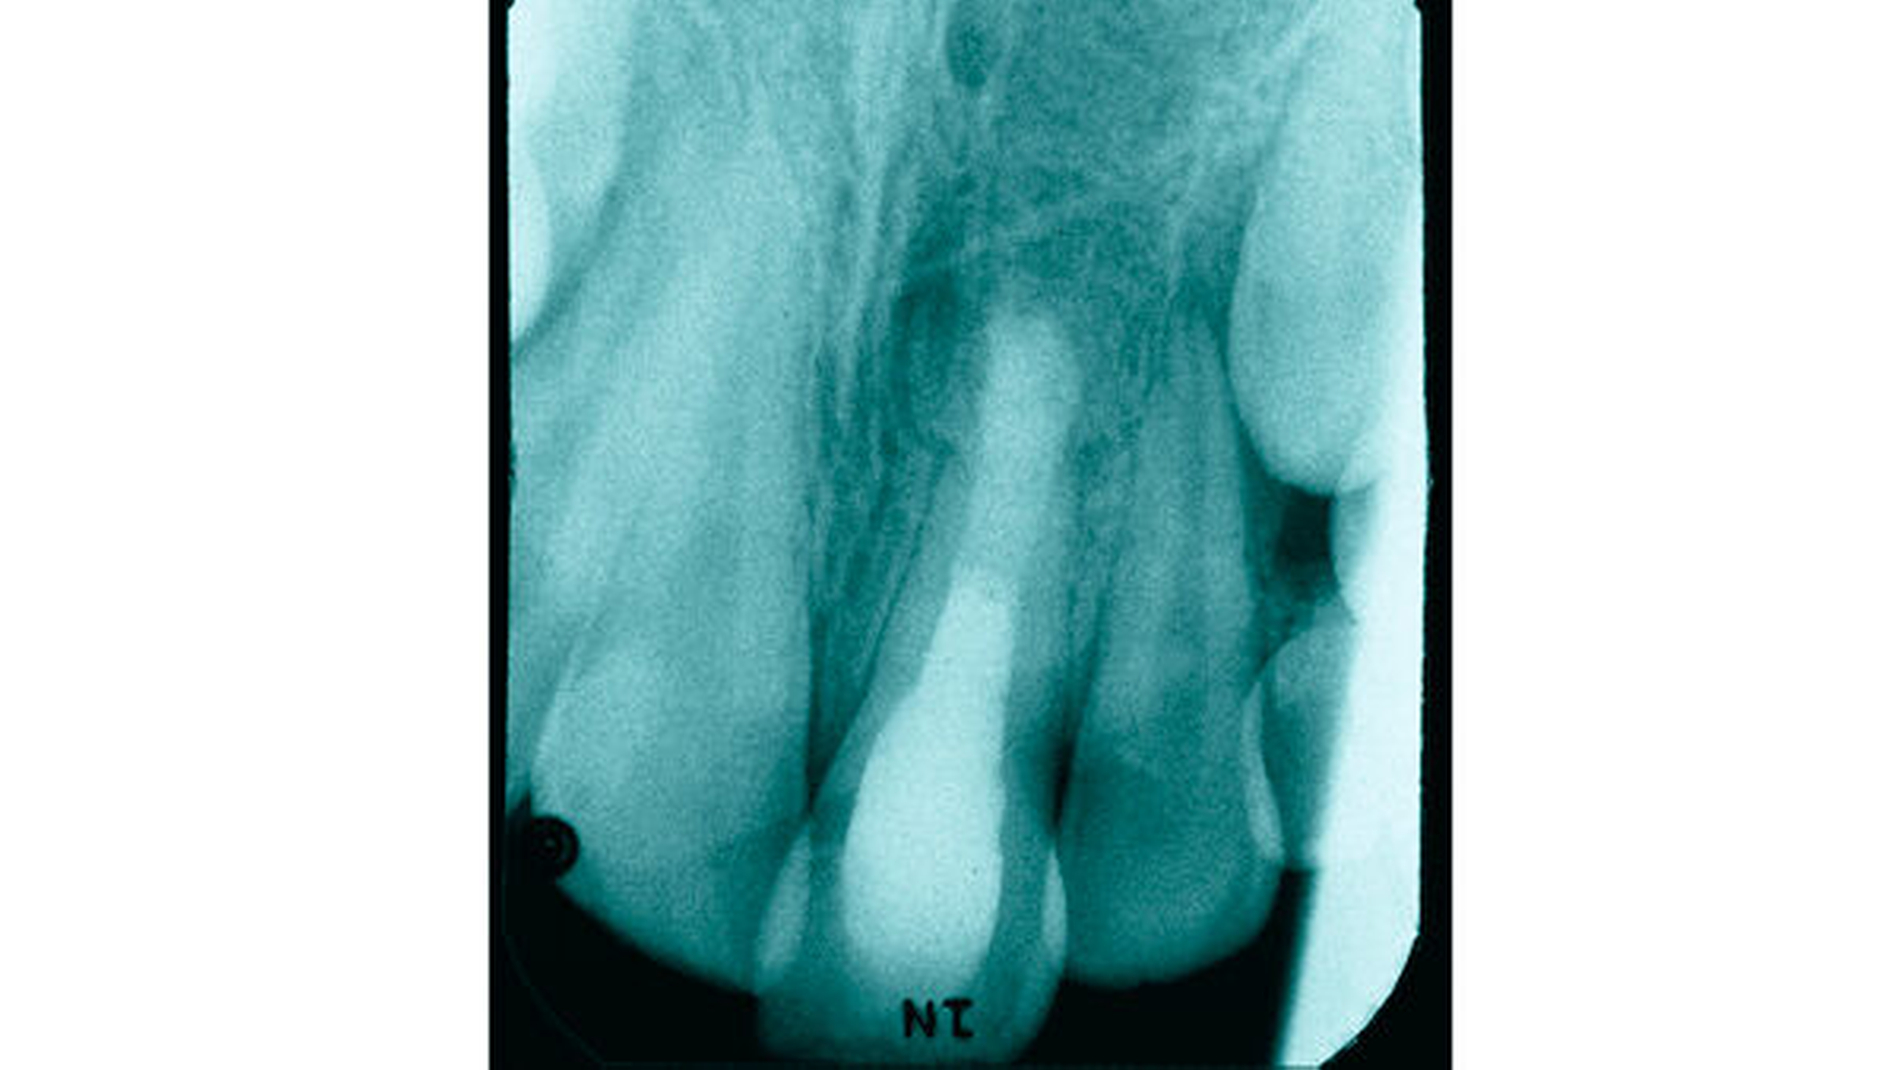

Da es zu keinen weiteren Beschwerden und zu einem komplikationsfreien Verlauf kam, stellte sich der Patient zu keiner weiteren Kontrolluntersuchung beim Zahnarzt am Heimatort vor. Zwei Jahre später bemerkte der Patient eine dezente Schwellung im Bereich der linken Oberlippe. Unter Schmerzen oder Aufbissempfindlichkeit litt der Patient dabei nicht. In diesem Zustand stellte sich der Patient in der Poliklinik für Zahnerhaltung des Universitätsklinikums Münster erstmals vor. Nach eingehender Anamnese und Befunderhebung wurde eine aktuelle Zahnfilmaufnahme angefertigt (Abbildung 2).

Auf der Zahnfilmaufnahme zeigte der Zahn 21 ein weiterhin nicht abgeschlossenes Wurzelwachstum und eine ausgedehnte apikale Osteolyse. Im Vergleich zur altersentsprechend entwickelten Wurzel des Zahnes 11 erschien die Wurzellänge des traumatisierten Zahnes verkürzt. Auch stellte sich das Lumen des Wurzelkanals im Seitenvergleich vergrößert dar. Nach eingehender Beratung und Aufklärung über die Befunde wurden dem Patienten die Therapiemöglichkeiten und Alternativen ausführlich erläutert. Aufgrund des Alters des Patienten wurde ein möglichst schonendes und atraumatisches Vorgehen angestrebt.